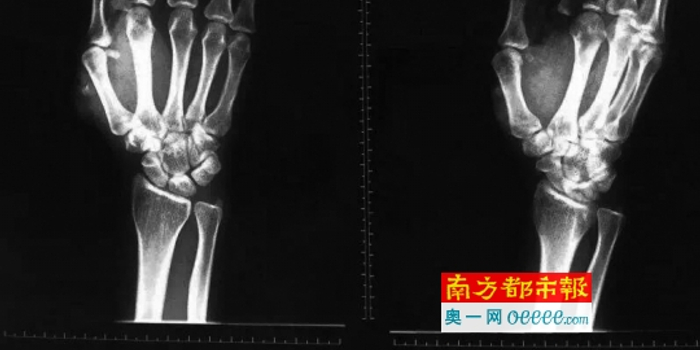

手术:右手拇指食指跟左肩胛骨最严重

主刀医生、中山一院显微创伤外科副主任朱庆棠说,欧丽志的右手拇指、食指多发骨折,肌腱、神经损伤,中指伸肌腱断裂;左肩的刀口很深,肩胛骨骨折,从肩部到上臂有20cm的刀伤,左臂有一条肌肉断裂;小腿也有刀伤。“伤得最重的是右手拇指、食指跟左侧肩胛骨。”

朱庆棠说,整个手术过程比较顺利,目前欧丽志的生命体征稳定,但因损伤比较多,恢复还要比较长时间,到底会恢复得如何还有待观察,手部功能可能会受影响。